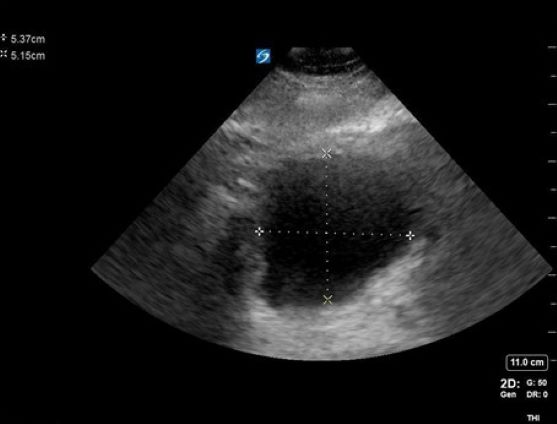

A 65-year-old male with a history of HTN, BPH, IDDM, and lumbar spinal stenosis presented to the ED with low back pain and lower extremity weakness. He denied fever, abdominal pain, and dysuria. He reports that he is able to urinate but unable to state if his urinary frequency has increased beyond “my normal prostate issues.” He notes he has fallen twice because “my legs just seem to give out on me.” On physical exam, he demonstrates 4+/5 bilateral LE strength, mild distal sensory loss, and absent patellar and Achilles reflexes. His rectal tone was equivocal. After use of a urinal, bedside POCUS was used to measure his post-void residual bladder volume:

Figure 1. A cross-sectional view of the bladder with AP and transverse measurements

Figure 2. A sagittal view of the bladder with cranial-caudal measurement

Figure 3. Calculation of bladder volume using the ellipsoid method (L x W x H x 0.52 = mL)

Findings concerning for Cauda Equina were all present in this patient’s history, physical exam, and workup. Current literature defines normal post-void bladder volume in adults as < 50 mL in patients under 65 years of age, and < 100 mL in those older than 65. Two hundred milliliters or greater is generally regarded as the threshold for retention.1 In this case, the patient was just on the cusp of normal vs abnormal post-void urinary volume, but with his other clinical signs and symptoms, warranted emergency spine consultation and MRI. Imaging eventually showed severe compression of the spinal nerve roots by discs at the L2-3 and 3-4 levels, necessitating emergent decompression.